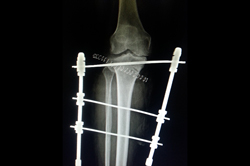

Deformity Correction - Genu Valgum